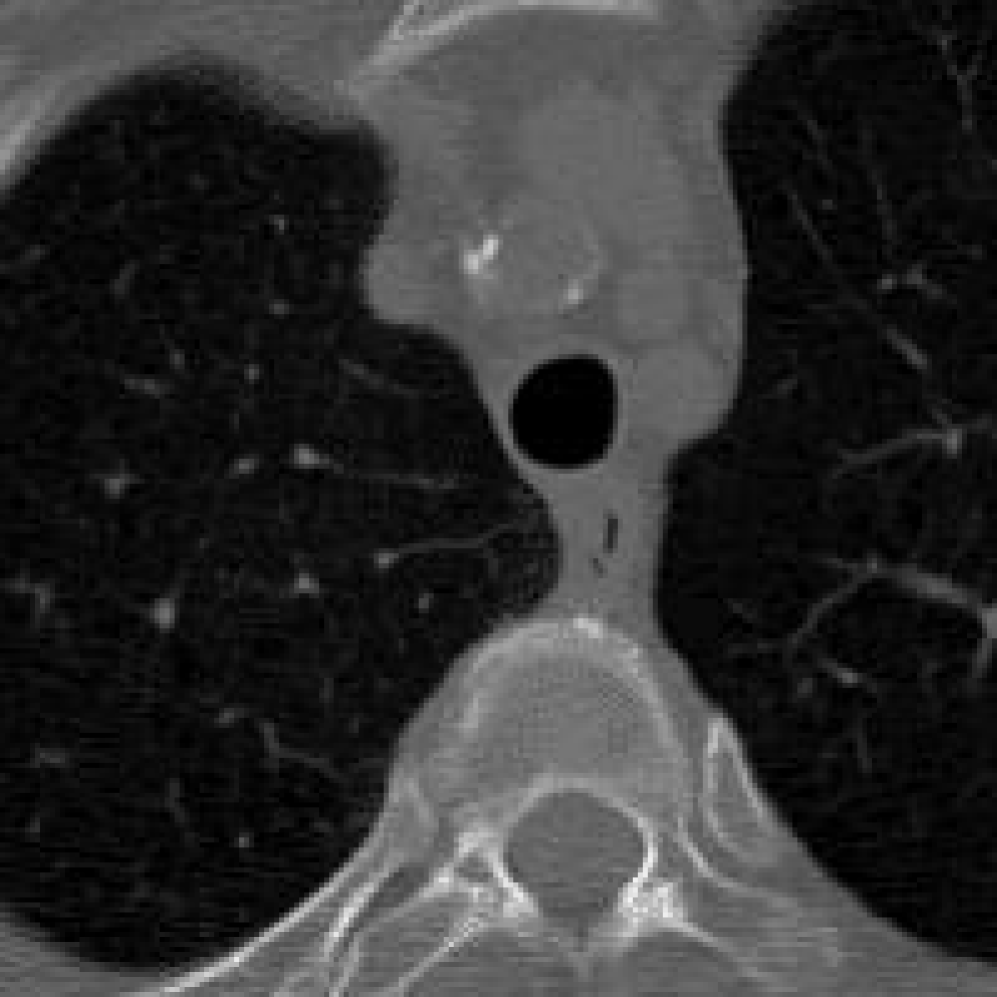

In addition, we use the CT Heart Segmentation dataset [NikhilTomar], which contains a series of 2D computed tomography (CT) heart scans with the resolution of 512 ×\times 512. This dataset provides clear anatomical structures of the human heart, and is widely used in medical image segmentation and compression tasks. Its inherent slice-based nature naturally aligns with our patch-based INR compression strategy, allowing us to further evaluate the effectiveness of COLI for medical images with rich structural information.

Figure 11: Zoomed-in view of the highlighted region in Figure 10.

IV-B3 Visual Comparison

Figures 7 and 8 present representative examples from the CIL dataset and their zoomed-in regions, respectively. For the CT Heart Segmentation dataset, Figures 10 and 12 illustrate typical reconstruction results, while Figures 11 and 13 further enlarge local regions to compare structural details. Across both datasets, COLI preserves fine structures and global continuity well even at relatively low bpp. Specifically, on the CIL dataset, COLI attains the lowest bitrate among INR-based methods while still maintaining clear texture details. On the CT Heart dataset, COLI also operates at a low bpp within the INR family and delivers superior visual quality with improved detail fidelity and smoother structural presentation. The zoomed-in regions show fewer blocking artifacts and smoother transitions, making COLI especially suitable for large images and medical images. These visual results validate that INR-based compression can achieve efficient storage with reliable perceptual consistency, offering practical advantages for real-world large-scale image processing.